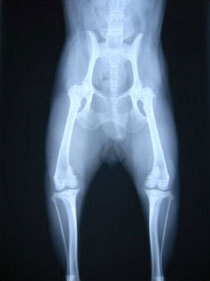

■ 症例24 キャバリア 7か月

左右膝蓋骨内方脱臼(左:グレードⅣ 右:グレードⅢ)

以前から左右後肢の跛行が認められ、整形外科学的検査・レントゲン検査により左右の膝蓋骨脱臼が認められた。症状が重度である左膝の膝蓋骨脱臼整復術を行った。外科手技は縫工筋及び内側広筋の解放、脛骨粗面の外側転位、滑車ブロック形造溝術、内外側関節方の縫縮を実施した。術後一か月時点で、左の膝蓋骨は安定しており経過は良好である。

本症例は成長期における重度の膝蓋骨脱臼であり、術後の再発の可能性もあるため、経過をしっかりと観察していく必要がある。また、今回手術を実施していない右膝に関しても経過を観察し、手術を検討していくこととする。